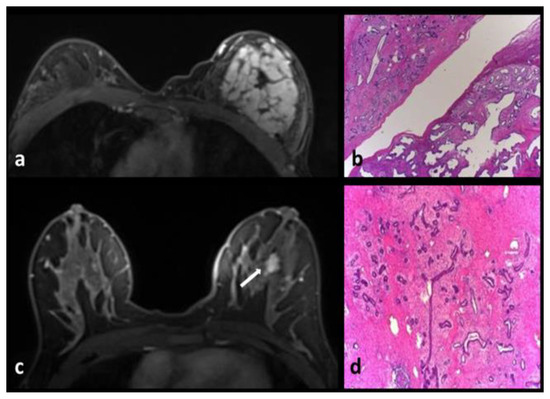

Adenomyoepithelioma

Fibrocystic Changes

Intraductal Papilloma-Intraductal Papillomatosis

Pseudoangiomatous stromal hyperplasia